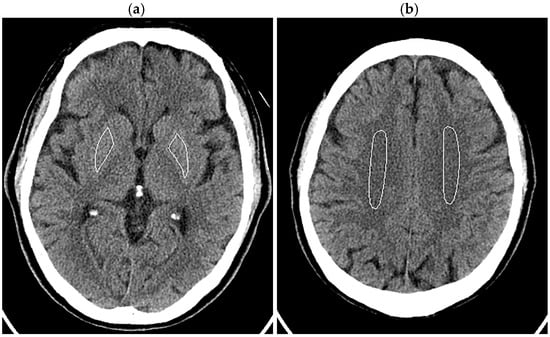

The patient’s head was imaged according to our routine clinical protocol. The tube current was modulated using inbuilt automatic exposure control software (Auto mA and Smart mA) with a noise index of 3.6, maximum mA of 350 mA, and minimum mA of 50 mA. Organ dose modulation was applied over the orbit to reduce radiation dose to the eye lens. This function selectively reduces radiation exposure from the anterior direction and does not change posterior exposure [31,32]. Image reconstruction was performed using FBP, three levels of DLR, and ten levels of HIR, similar to the phantom experiments. In image analysis, ROIs were manually drawn in bilateral lenticular nuclei (right 166.5 ± 26.6 mm2, left 158.5 ± 29.3 mm2), avoiding calcifications in the globus pallidus, and centrum semiovales (right 449.6 ± 136.0 mm2, left 432.6 ± 98.5 mm2) (Figure 2). The SD was obtained for each ROI, and the mean of the right and left values was defined as the image noises for the lenticular nucleus and centrum semiovale. Noise reduction ratios were calculated using the image noise for the FBP images as the reference.

Figure 2.

ROIs in the lenticular nuclei (a) and centrum semiovales (b) displayed on the 5 mm thick FBP images of the head of a 70-year-old male patient.